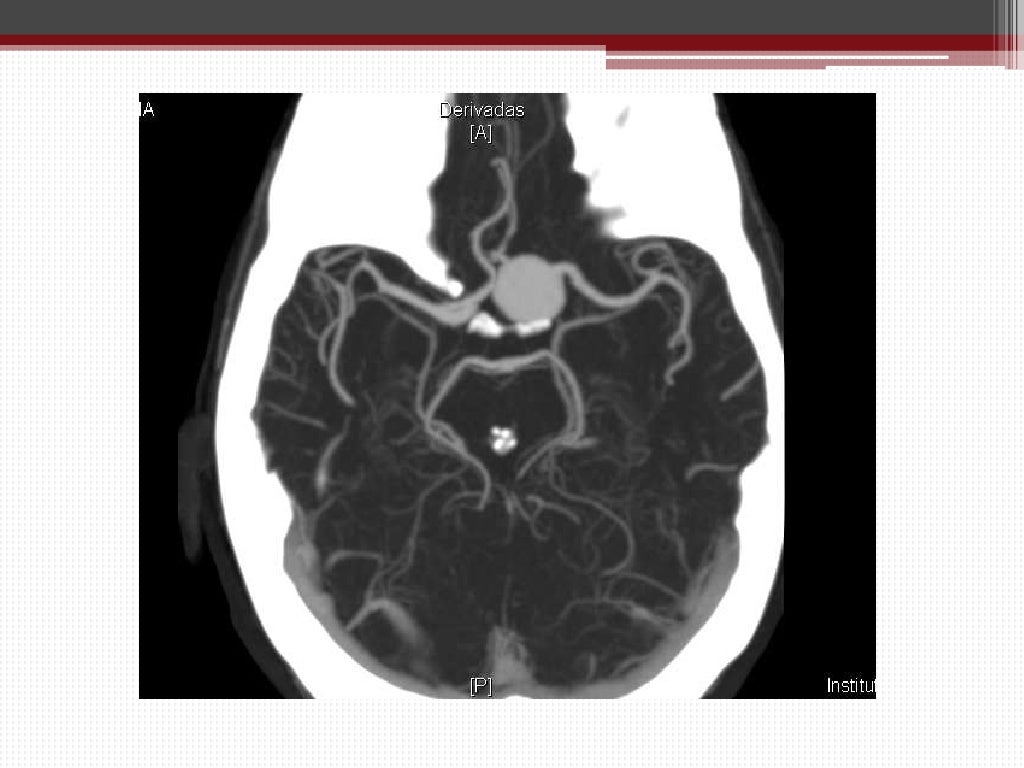

Estudio de aneurisma cerebral mediante angio tc

Ver índice. No contexto do estudo vascular intracraniano, as técnicas angiográficas por tomografia computadorizada (TC) e ressonância magnética (RM) têm papel de bastante destaque. As imagens de angio-TC e angio-RM têm aproximado cada vez mais daquelas da angiografia com subtração de imagens digitais, que ainda são consideradas.